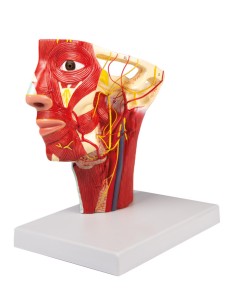

Scopri il Mondo dell’Anatomia con Modelli anatomici di Precisione

Benvenuto su Tuttoanatomia.it, il portale di riferimento in Italia per l’acquisto di modelli anatomici, poster, lettini portatili, simulatori medici e letteratura specialistica. Con i nostri modelli anatomici di 3B Scientific ed Erler Zimmer, leader mondiali nel settore, offriamo un’esperienza di apprendimento senza pari.

Modelli Anatomici Dettagliati per Ogni Necessità

Dal cranio in 22 parti con incastri magnetici ai modelli di colonna vertebrale, da quelli di articolazioni a quelli di cuore, ogni pezzo della nostra collezione è progettato per un’immersione totale nello studio dell’anatomia umana. I nostri modelli, realizzati tramite scansioni di ossa vere, garantiscono un’esperienza tattile autentica e una fedeltà di peso quasi identica agli originali.

Strumenti Didattici Innovativi per l’Educazione e la Pratica Medica

Essenziali per studenti e professionisti, i nostri modelli anatomici sono strumenti didattici che permettono di osservare le strutture anatomiche con precisione, eliminando la necessità di dissezioni o studi invasivi. Sono inoltre utili per spiegare ai pazienti le patologie, rendendo la comunicazione più efficace e risparmiando tempo prezioso.